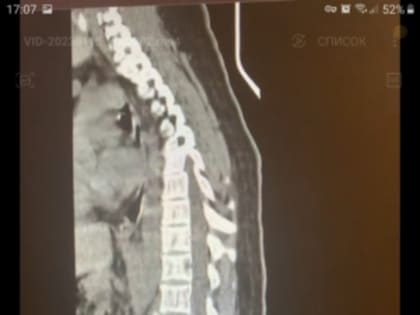

Клинический случай. Травма после катания на тюбинге.

Новый клинический случай у травматологов КМКБСМП. Молодая женщина была доставлена в больницу с травмой позвоночника, которую получила во время спуска с горы на тюбинге.